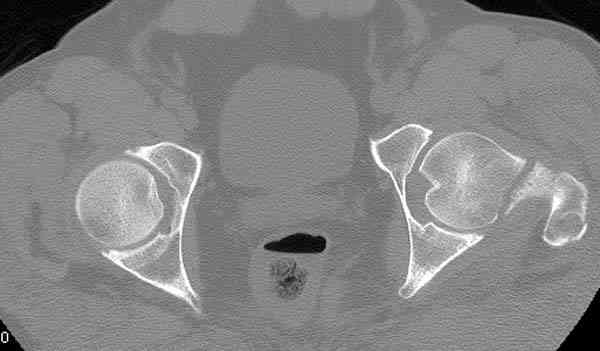

Здесь представлены снимки больного 65 лет, поступившего с диагнозом перелом

бедра после автоаварии.

На второй день (7) обнаружен пропущенный перелом,

сделаны Компьютерная Томограмма